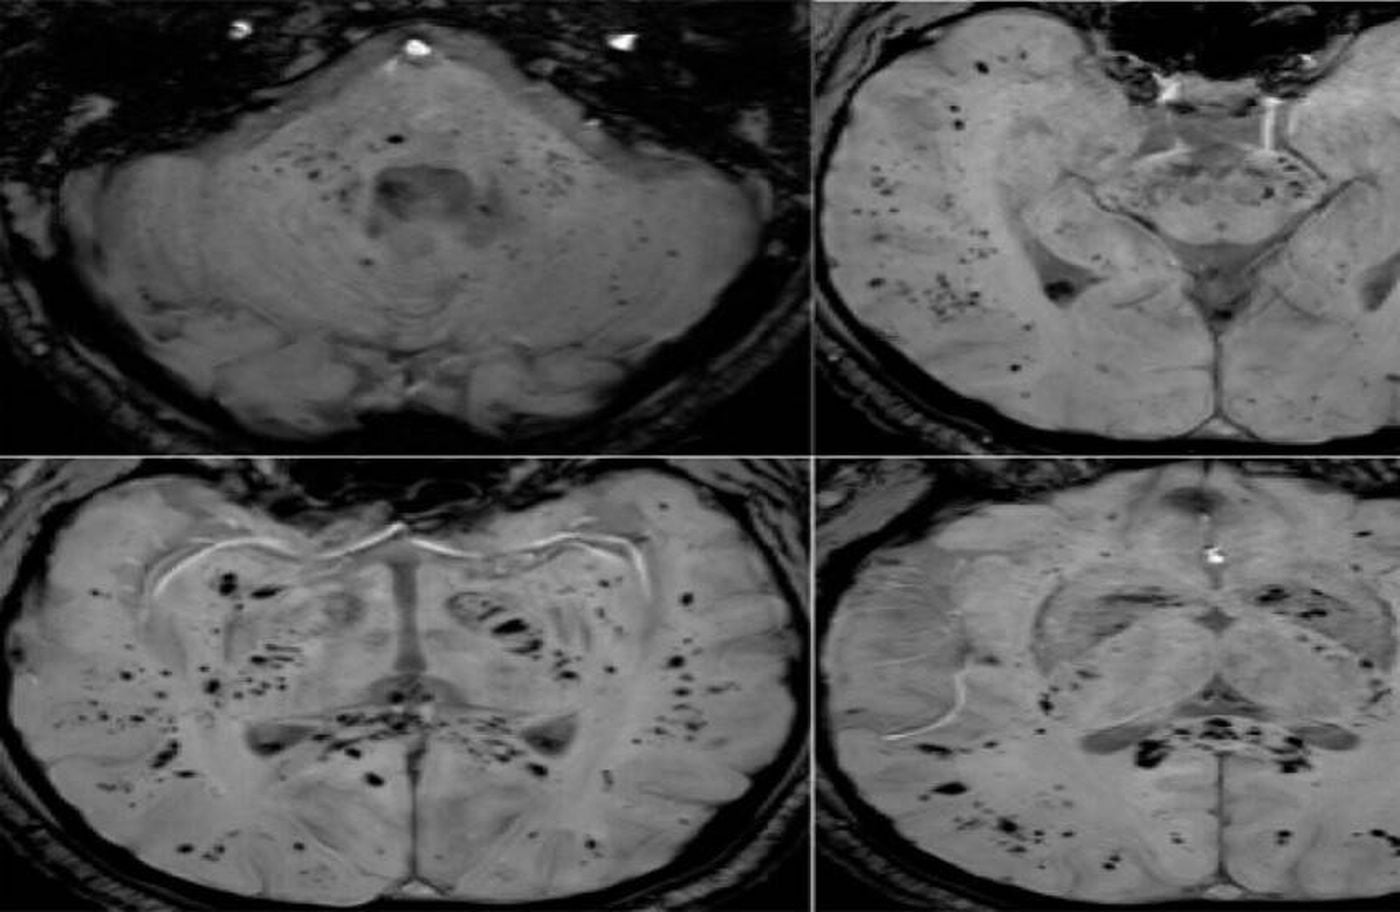

الرنين المغناطيسي يكشف تأثير كوفيد-19 على الدماغ